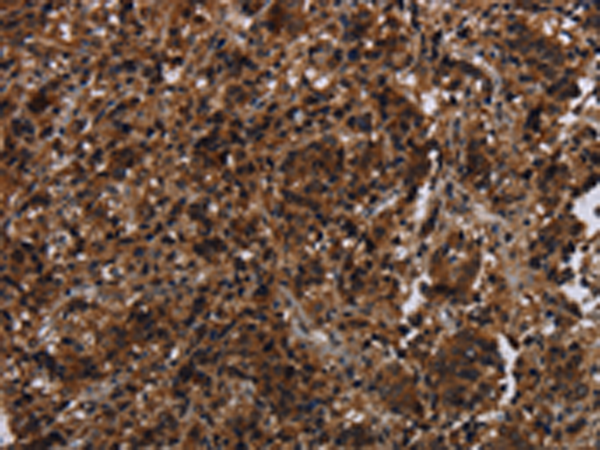

分类: 科研抗体货号: P05035别名: HCA1; DAMAGE应用: WB,IHC反应种属: Human